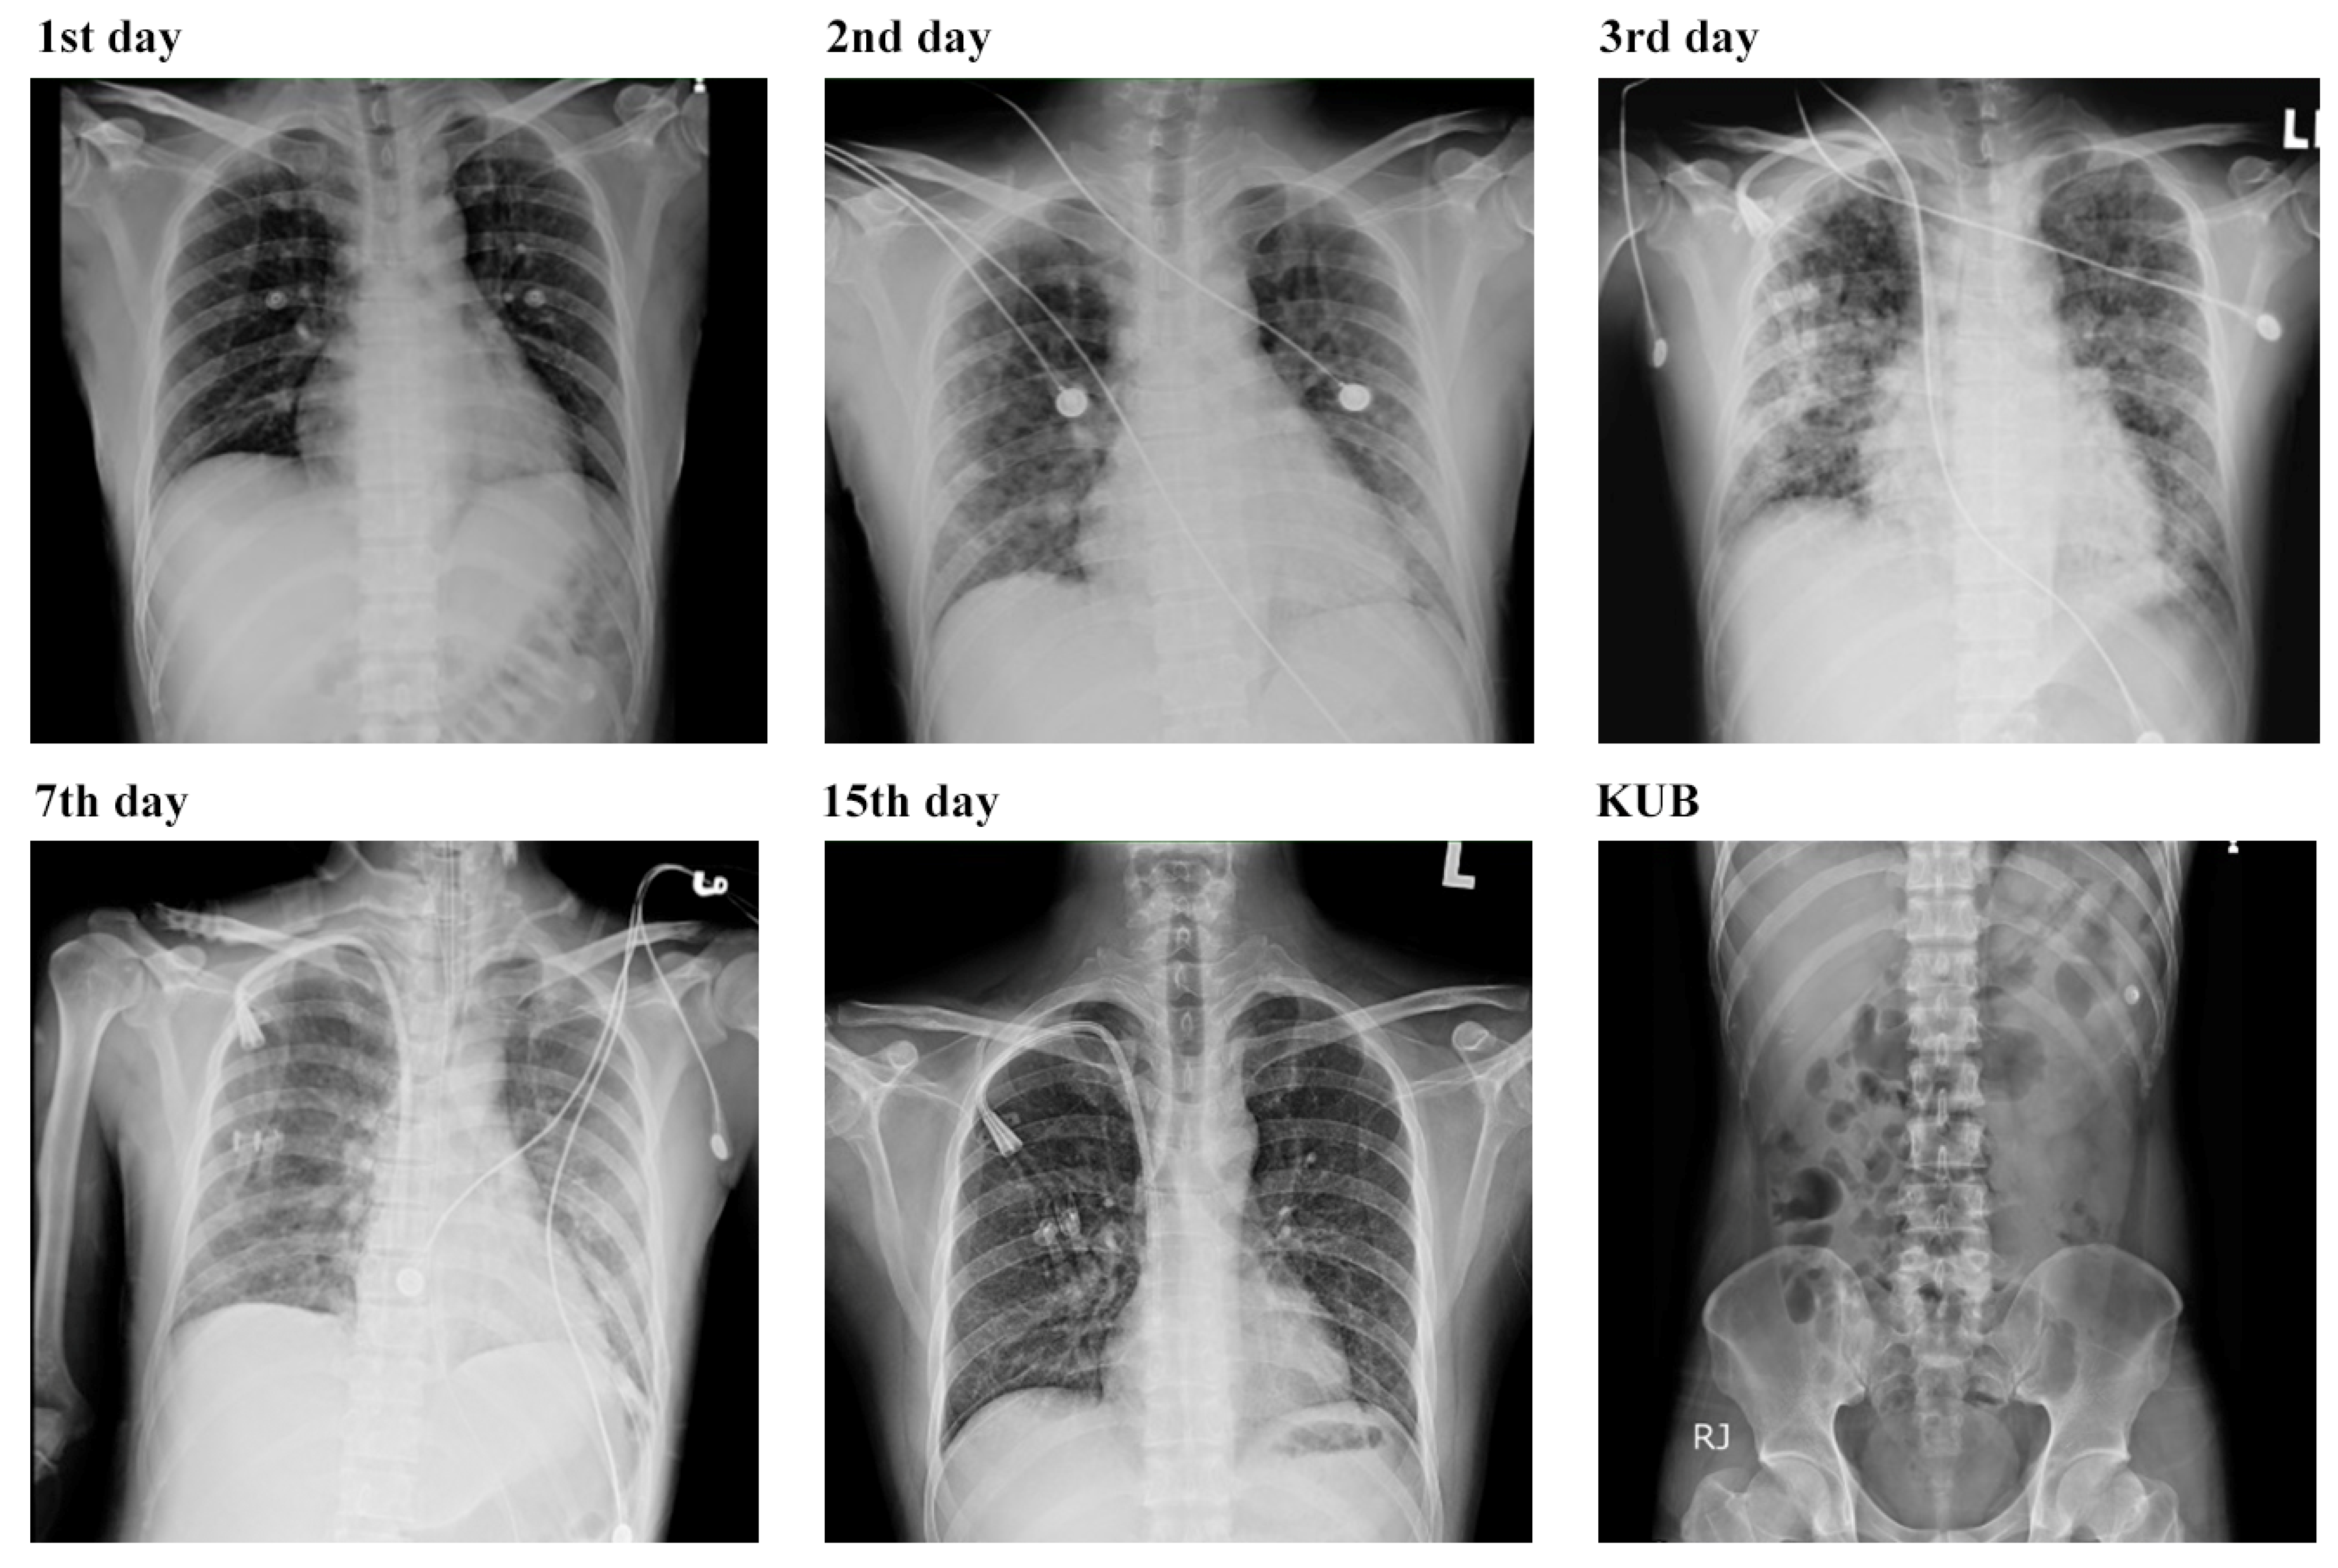

3.3. Respiratory Complications and Multifaceted Treatment Outcome of Leptospirosis